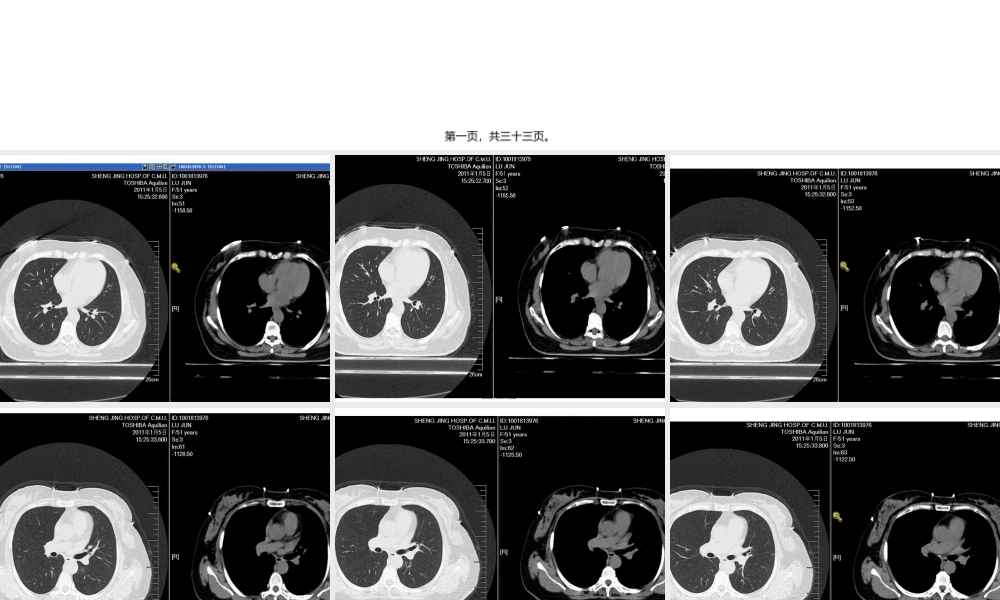

肺癌筛查指南NationalComprehensiveCancerNetworkVersion1.2022第一页,共三十三页。第二页,共三十三页。第三页,共三十三页。第四页,共三十三页。第五页,共三十三页。第六页,共三十三页。第七页,共三十三页。第八页,共三十三页。第九页,共三十三页。第十页,共三十三页。是否为恶性?会不会恶变?需要复查吗?第十一页,共三十三页。美国国家综合癌症网〔NCCN〕指出,在美国和世界其它国家,癌症相关的死亡数量中,肺癌是最主要的死因。据估计2022年,在美国,肺癌将导致156900人死亡〔男性85600,女性71300〕。肺癌的5年生存率仅约15.6%,一局部原因是大局部病人在初次就诊时已是肺癌晚期。第十二页,共三十三页。对子宫颈癌、结肠癌、乳腺癌的筛查以改善疾病预后,这些成功经验是开展一种有效的肺癌筛查测验的推动力。理想目标是,有效的筛查会早期检测出肺癌,并在患者出现病症前,这时治疗更可能有效,减少死亡率。目前,大局部肺癌是在患者有病症时作出临床诊断,如出现咳嗽、胸痛、体重减轻。很不幸,有这些病症的患者通常是晚期肺癌。第十三页,共三十三页。美国NCCN〔国家综合癌症网〕于2022年10月底首次发布了肺癌筛查指南,指南的发布是基于新英格兰医学杂志〔NEJM〕于2022年8月发表的美国国立肺癌筛查研究〔NLST〕的结果。该研究对高危人群应用低剂量螺旋CT〔LDCT〕做每年常规检查,结果发现,与胸片体检相比,LDCT体检可以使肺癌死亡率降低20%,使任何原因死亡率降低7%。基于这一结果,指南中明确将LDCT作为肺癌筛查手段,并对LDCT上的不同发现做出了不同的处理指南。第十四页,共三十三页。总的来说,NCCN指南建议对肺癌高危人群每年进行肺部低剂量螺旋CT检查。高危人群是指:A.55-74岁,正在吸烟或者戒烟少于15年,并且吸烟指数大于30包年。B.年龄≥50岁,吸烟指数≥20包年,并且合并以下情况之一者:肿瘤病史;肺病史;家族中有肺癌患者;住所氡暴露和致癌物质的职业性暴露〔包括砷、铬、石棉、镍、镉、铍、二氧化硅和柴油烟气〕。以上肺癌高危人群建议每年行低剂量螺旋CT〔LDCT〕检查,最少3年〔最佳答案持续年限尚不清楚〕。第十五页,共三十三页。中危人群:年龄≥50岁,吸烟指数≥20包年,或有二手烟暴露,没有附加的危险因素。低危人群:年龄<50岁和/或吸烟指数<20包年。以上不推荐常规肺癌筛查第十六页,共三十三页。根据CT检查结果不同采取不同的处理措施A.未发现肺部结节:每年LDCT检查,至少持续3年〔最佳答案持...